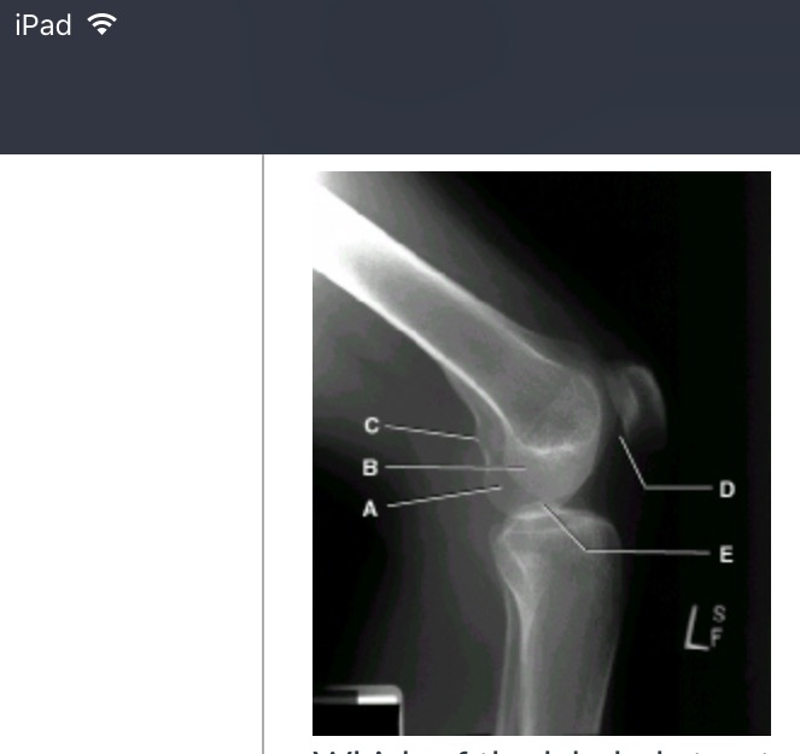

card image

which one of the labeled structures is the medial condyle? (picture)

a